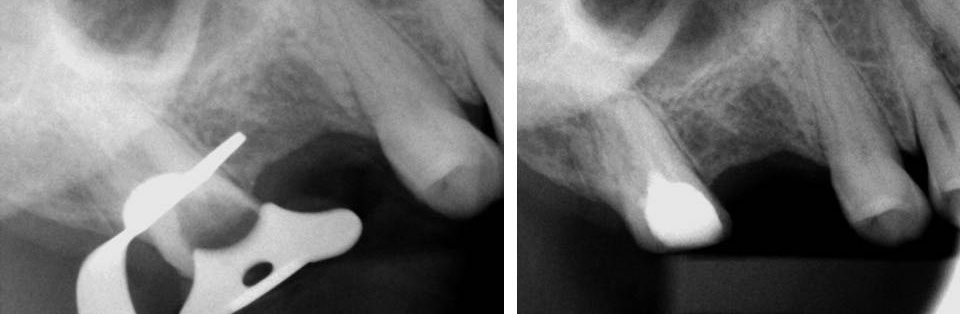

Pre-op

Perforation (red arrow)

Post-op